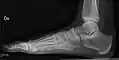

- Ankle - AP/Mortice and Lateral

-

Ankle - frontal -

15 degrees internal rotation -

Lateral (this one a bit suboptimal by not seeing straight through the ankle joint) -

Lateral oblique (to visualize the posterior border of the tibia)

- Foot / Toes - Dorsoplantar, Oblique and Lateral.[19]

Normal right foot by dorsoplantar projection -

Oblique projection -

Lateral projection